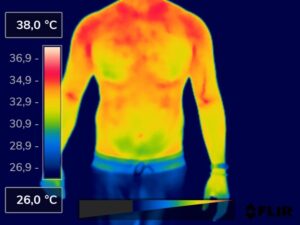

Como na sequência de termogramas abaixo de um paciente do sexo masculino, de 44 anos, sem comorbidades e praticante de atividade física que apresentou fortes dores em braço esquerdo (com irradiação para antebraço) após treino de musculação. Esta dor chegou a ser incapacitante, pois impossibilitava inclusive o paciente a realizar atividades de vida diárias como pegar um copo de água.

Após a realização de uma Análise Termofuncional©®, foi detectado alterações térmicas em “linha”, margeando as fibras musculares e tendíneas inferiores (insercionais) bicipitais. Estas alterações também aventaram a hipótese de dilatação venosa, por alguma reação inflamatória local. Foi realizado então aplicação de laserterapia através da Técnica Termoguiada, que acabou por promover a completa analgesia em 24 horas após aplicação.